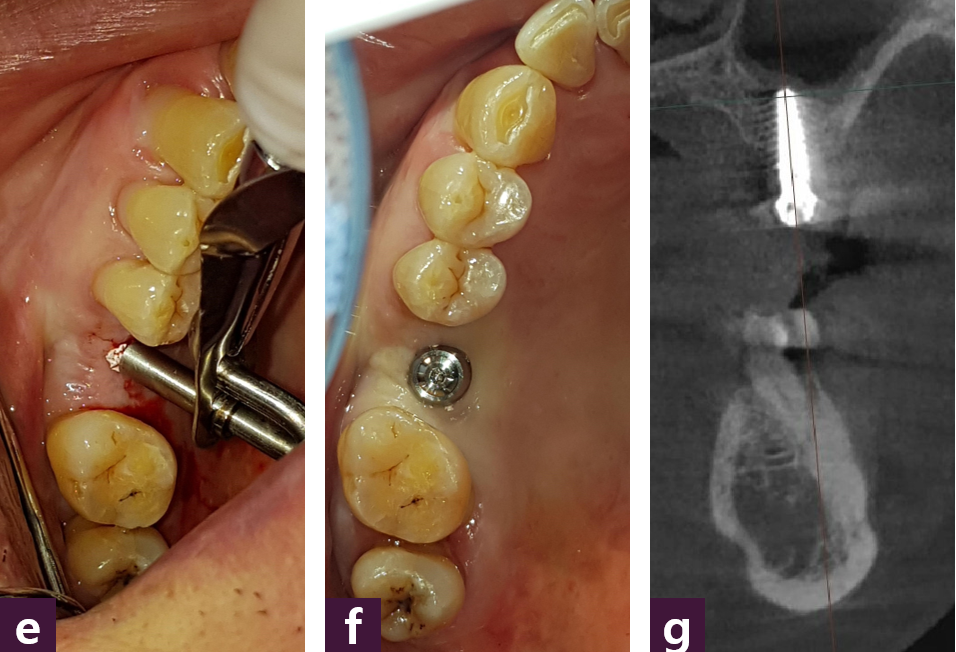

[3] AMII Guide Implant Doing

(# AMII Guide는 8가지 module로 구성되나, 지면 관계상 #Module GG(Guide GPS)만을 소개합니다.) # Module GG(Guide GPS) 실천 과정은 adaptation, guide GPS, verify, MFD, MFI, confirm 등의 6단계로 진행된다 [그림 9].

술 전에 직경 1mm, 길이 4mm의 Magic Guide Pin을 장치를 이용하여 지정된 위치 에 삽입하고 CBCT를 통해 안전확보가 확인되면 “거침없이” 진행하는 MagiCore의 GPS (Guide Pin System)은 단순하면서도 획기적인 치료 방법으로 충분히 검증되어 왔다.

여기에 가상 현실을 덧입힘으로써 기존 가이드 임플란트 수술의 한계를 완벽하게 극 복하는 “술 중 검증 가능한 가이드” 임플란트 수술 시대의 서막이 열리고, 마침내 어떤 종류의 수술 가이드라도 그 가이드 위에 “Guide 위에 Guide를 더하다!”는 개념의 최소 침습 임플란트 MagiCore 시스템의 GPS를 덧입히는 수술 방법의 선택이 가능해지면서 우리의 진료 현장은 안전하고(safe), 깔끔하며(simple), 신속한(speed) “3S implantation” 으로 진화하면서 환자와 술자의 만족감도 더욱 높일 수 있게 되었다.